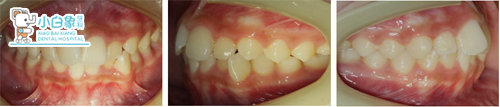

治疗计划:

全口直丝固定矫治术(普特自锁)

排齐与整平牙弓

先保守治疗,治疗半年后再决定是否拔牙(牙齿排齐后,家长觉得面型可以,故不拔牙矫治)

解决覆合覆盖关系

精细调整

保持

治疗后

治疗前后对比